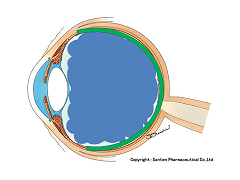

黒目(角膜)から入ってきた光は、目の奥の方のフィルム(網膜)に当たります。網膜は一つの束(視神経)になって、最終的には脳ミソにつながり、「物が見える」という事になります。

図の赤矢印の部分は視神経乳頭と言って、網膜が集まって束になる部分なのですが、実はこの部位のみ光を感じ取ることはできないのです。